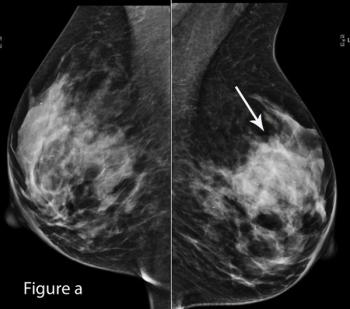

53-year-old BRCA2 positive patient presented for bilateral screening breast MRI.